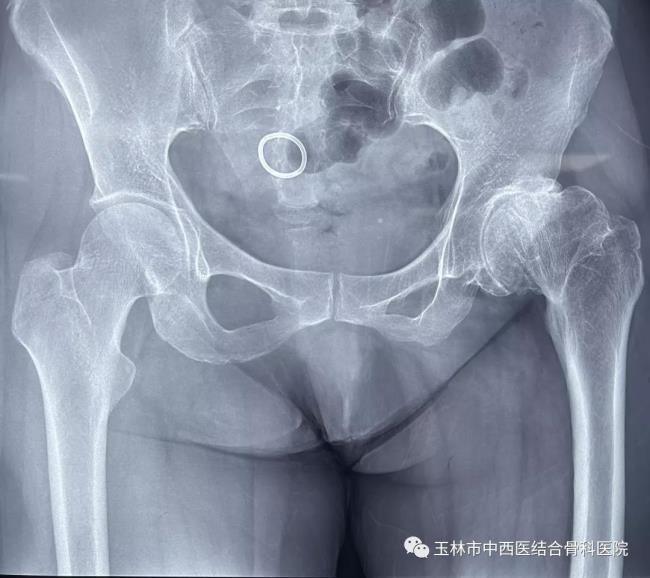

图三:术前

图四:术后

女性患者张某,44岁。经诊断为:左髋关节骨性关节病。这种疾病因为骨的退化、磨损,无特效药物治疗,目前手术治疗为最佳的治疗手段。由于该患者髋臼发育不良,髋关节挛缩,也就是说不同于正常的髋关节结构。手术是用人工的髋关节来代替现有关节,重新建立正常髋部结构,要求达20到30年乃至更久的使用寿命。如果手术中髋臼重建的位置、角度、深度任何一方面不精确,都将造成人工关节安装失败,进而影响它的使用寿命。手术难度大,技术要求高。微创髋关节置换(DAA)手术量超过1000多例的黎观保主任表示,仍然可以用微创手术技术来解决。

黎主任根据患者的病情,制定了独特的手术方案,就是在传统微创髋关节置换(DAA)技术基础上更进一步,使用anterior path技术,既比基尼切口(bikini incision)结合通道经髋前侧肌肉间隙做微创的髋关节置换。这与常规的手术相比,更容易做到小切口下充分显露髋臼和股骨侧,减少创伤,提高人工关节安装的精确度。手术时间约1小时,出血约100ml。患者术后第一天下地活动,自我感觉良好。